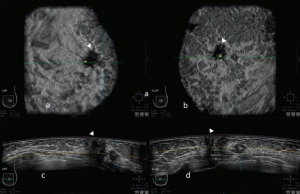

سونوگرافی سینه (Breast ultrasound)

سونوگرافی پستان اغلب برای بررسی وجود برخی از انواع تغییرات پستانی استفاده میشود.

سونوگرافی سینه از امواج صوتی برای ایجاد تصویر کامپیوتری از داخل سینه استفاده میکند. یک ژل روی پوست سینه مالیده میشود و ابزاری گرز مانند به نام مبدل (transducer) روی پوست حرکت میکند.

مبدل امواج صوتی را میفرستد و پژواکها را هنگامی که از بافتهای بدن منعکس میشوند، دریافت میکند. پژواکها به یک تصویر روی صفحه کامپیوتر تبدیل میشوند. ممکن است زمانی که مبدل در سینه حرکت میکند فشاری را احساس کنید اما نباید دردناک باشد. این آزمایش شما را در معرض تشعشع قرار نمیدهد.

سونوگرافی پستان اغلب برای بررسی تغییرات پستان که در طول ماموگرافی یا معاینه فیزیکی پیدا میشوند، استفاده میشود. این روش مفید است زیرا اغلب میتواند تفاوت بین کیستهای پر از مایع (که بعید به نظر میرسد سرطان باشند) و تودههای جامد (که ممکن است برای اطمینان از سرطانی نبودن آنها به آزمایش بیشتری نیاز داشته باشند) را تشخیص دهد.

در فردی که تومور سینه دارد، از سونوگرافی نیز میتوان برای بررسی بزرگ شدن غدد لنفاوی زیر بازو استفاده کرد. در صورت وجود، میتوان از سونوگرافی برای هدایت سوزن برای گرفتن نمونه (بیوپسی) برای جستجوی سلولهای سرطانی در آن جا و در بافت پستان استفاده کرد.